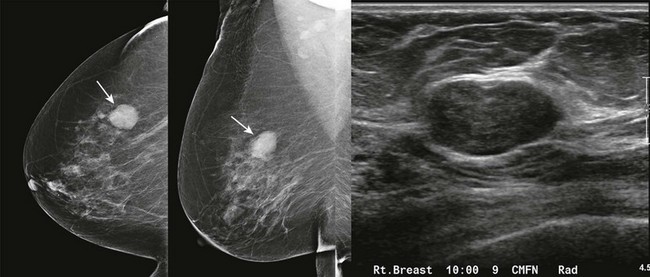

CASE 8-6. There are multiple bilateral masses. However, the findings cannot be considered benign because one mass, in the upper-outer quadrant of the right breast (arrows), has enlarged markedly since the previous mammogram and, therefore, warrants diagnostic evaluation. US shows an oval, circumscribed, solid mass with parallel orientation in the 10 o’clock position. Biopsy is indicated because of the rapid enlargement of the mass. Core biopsy revealed benign phyllodes tumor associated with lobular carcinoma in situ with the same diagnosis at excision.